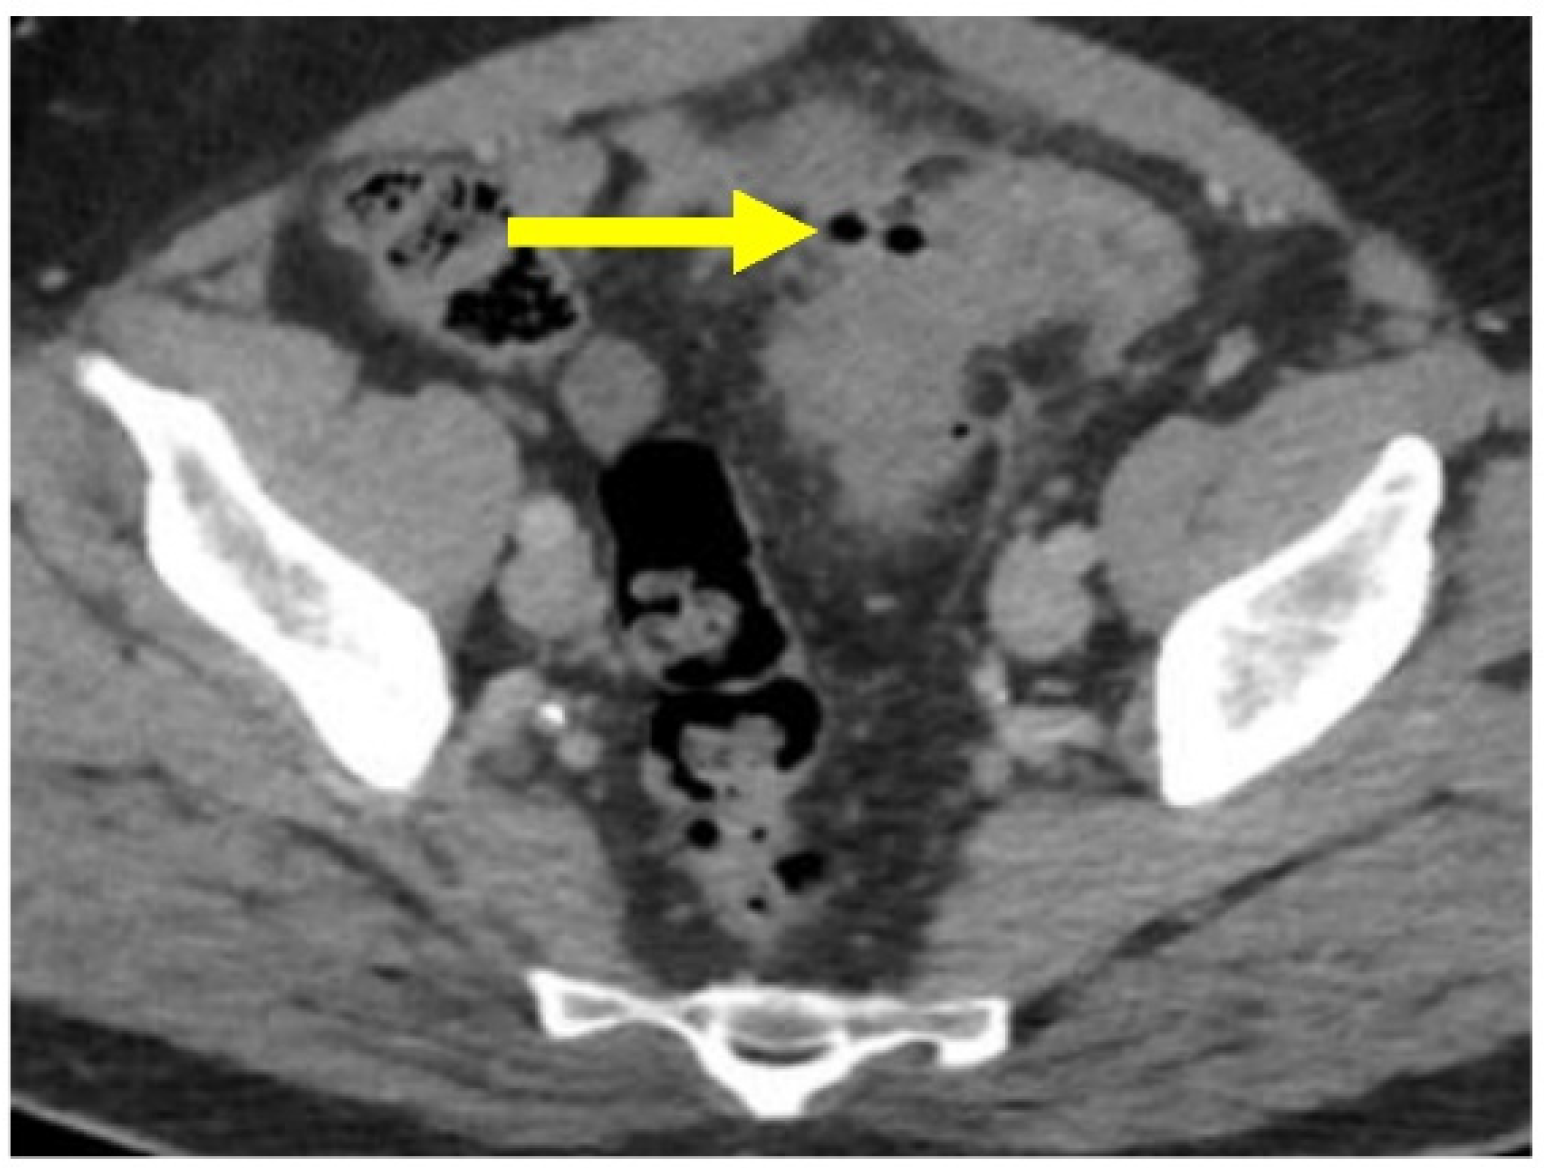

Most patients (~90%) will have uncomplicated diverticulitis, characterized by localized inflammation limited to the colonic wall and surrounding tissue. Patients present with fever, abdominal pain, and/or leukocytosis [4,26]. On CT imaging, there is evidence of inflammatory stranding within the peridiverticular fat without evidence of free air or an adjacent fluid collection (Figure 4).

Figure 4.

Acute uncomplicated sigmoid diverticulitis. Axial CT image through the pelvis with oral and IV contrast. There is extensive sigmoid diverticulosis. There is inflammatory stranding within the fat (yellow arrow), which is centered on a sigmoid diverticulum (black arrow). There is no evidence for free air or adjacent fluid collection.